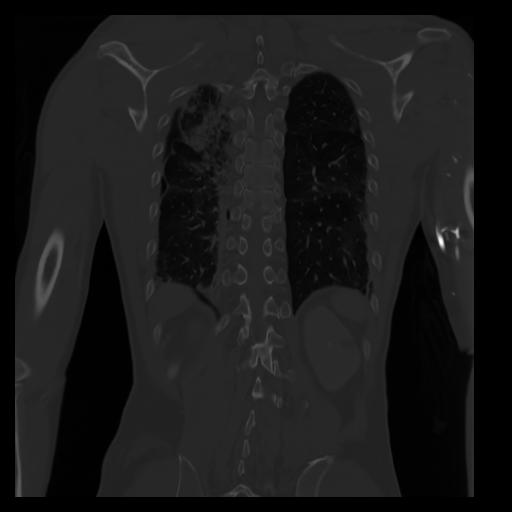

29 CUERPO,CE,Coronal,3.000,CUERPO,Coronal,